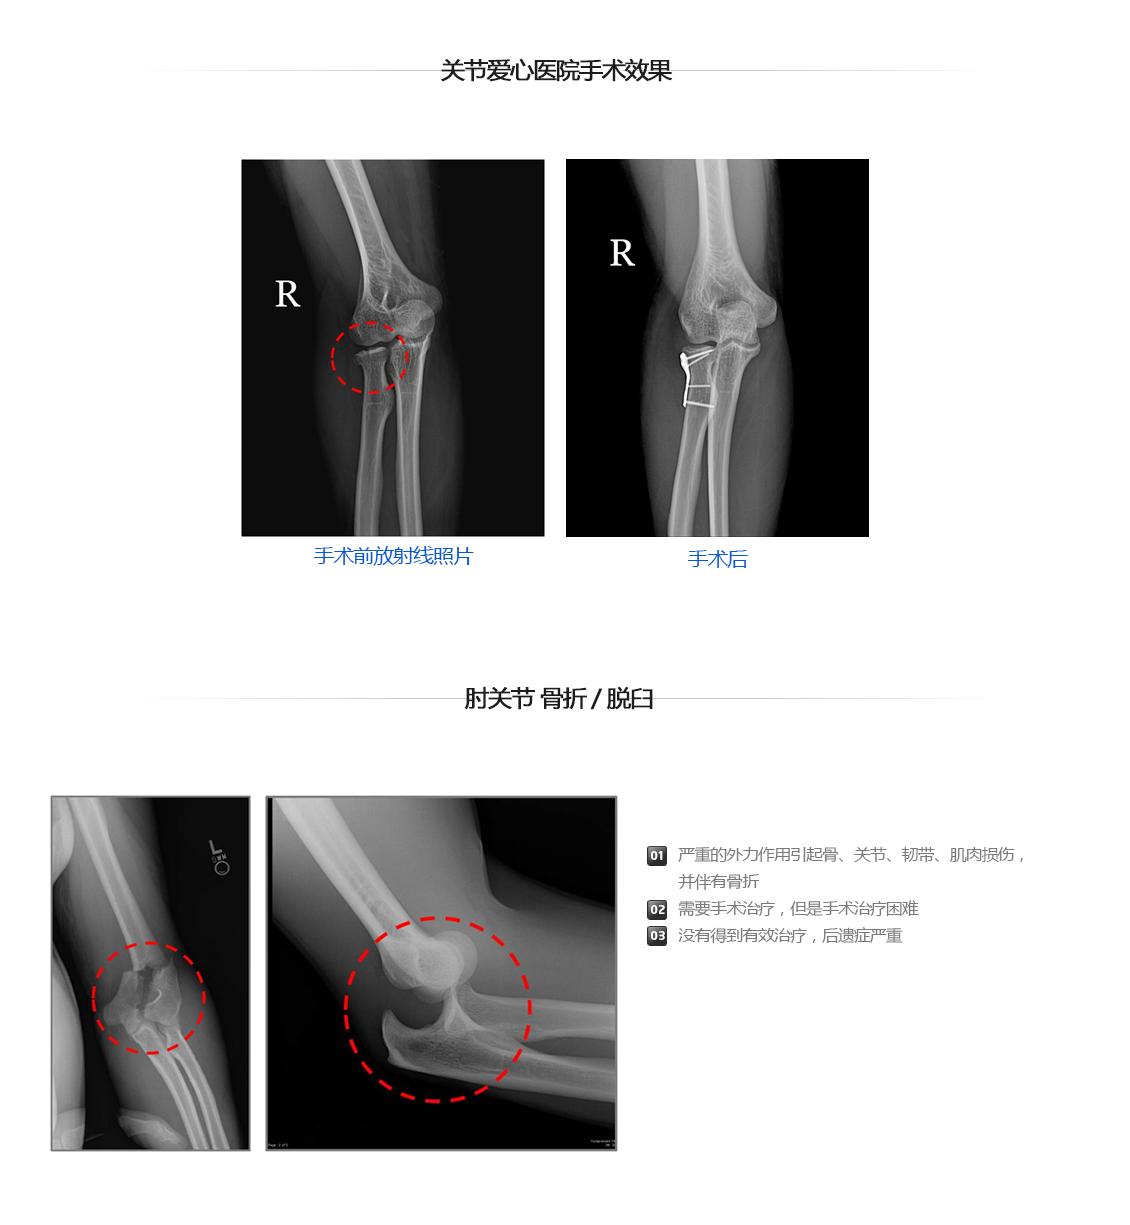

胳膊肘关节骨折